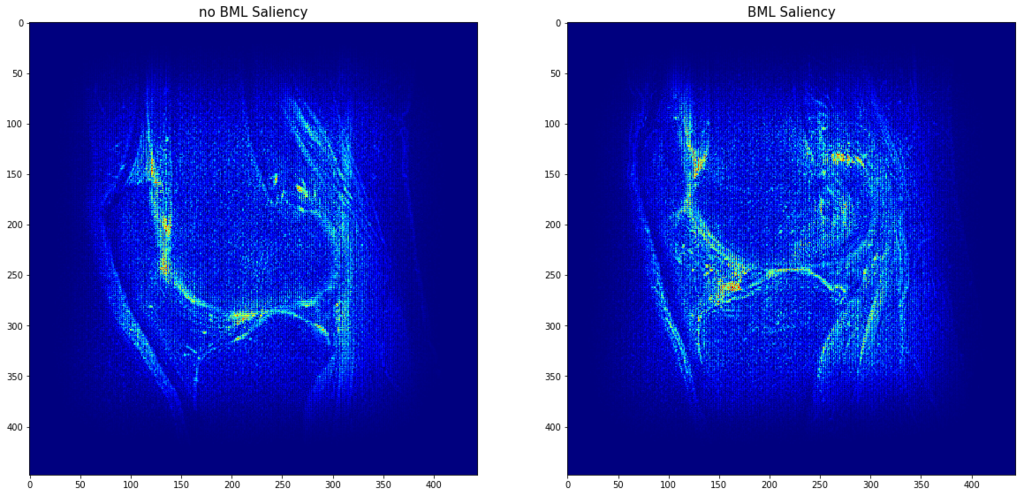

Bone marrow edemas (BMEs) are defined as localized build-up of fluids within the bone marrow, often leading to swelling, which are strongly associated with pain and progression of joint deterioration. However, manual reading of BMEs is a time-consuming task for the physician. Here, we ask if a deep neural network can automatically detect the presence or absence of BME from T2 sequences of Magnetic Resonance images.

We collected 24.885 MRI sequences from the OAI study with associated labels of 10.429 for BMEs in the form of MOAKS scores. Sequences were classified for the presence of BMEs if the total number of BMEs exceeded 1 and its reported size of less than 33% in the respective compartment. This dataset was split into training/testing datasets of sizes 773 and 465, respectively. A deep neural network was trained on 1083 training/validation splits of the training dataset. Training performance was assessed by classification accuracy and testing performance was assessed by the area under the ROC curve (AUC).

Results

The final training accuracy on the training/validation datasets was 1 and 0.81. We find that our deep neural network achieves an AUC of 0.90 on the testing dataset at the detection of BMEs from T2 MRI sequences. Furthermore, saliency analysis reveals the location of these BMEs.

Conclusion

Our results show that our method performs excellently at detecting BMEs from MRI. This automated method assesses a full MRI sequence under 2 seconds and, combined with automatic highlighting of the detected BMEs, can substantially decrease physicians’ time spent on this routine task.